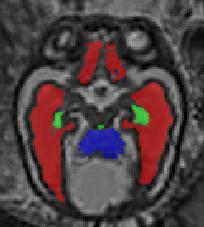

Limiting failures of machine learning systems is of paramount importance for safety-critical applications. In order to improve the robustness of machine learning systems, Distributionally Robust Optimization (DRO) has been proposed as a generalization of Empirical Risk Minimization (ERM). However, its use in deep learning has been severely restricted due to the relative inefficiency of the optimizers available for DRO in comparison to the wide-spread variants of Stochastic Gradient Descent (SGD) optimizers for ERM. We propose SGD with hardness weighted sampling, a principled and efficient optimization method for DRO in machine learning that is particularly suited in the context of deep learning. Similar to a hard example mining strategy in practice, the proposed algorithm is straightforward to implement and computationally as efficient as SGD-based optimizers used for deep learning, requiring minimal overhead computation. In contrast to typical ad hoc hard mining approaches, we prove the convergence of our DRO algorithm for over-parameterized deep learning networks with ReLU activation and a finite number of layers and parameters. Our experiments on fetal brain 3D MRI segmentation and brain tumor segmentation in MRI demonstrate the feasibility and the usefulness of our approach. Using our hardness weighted sampling for training a state-of-the-art deep learning pipeline leads to improved robustness to anatomical variabilities in automatic fetal brain 3D MRI segmentation using deep learning and to improved robustness to the image protocol variations in brain tumor segmentation. Our code is available at https://github.com/LucasFidon/HardnessWeightedSampler.